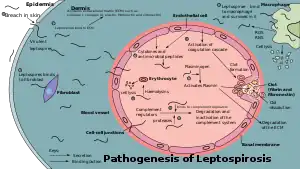

Pathogenesis

When animals ingest the bacteria, they circulate in the bloodstream, then lodge themselves into the kidneys through the glomerular or peritubular capillaries. The bacteria then pass into the lumens of the renal tubules and colonise the brush border and proximal convoluted tubule. This causes the continuous shedding of bacteria in the urine without the animal experiencing significant ill effects. This relationship between the animal and the bacteria is known as a commensal relationship, and the animal is known as a reservoir host.[20]

Humans are the accidental host of Leptospira.[5] The pathogenesis of leptospirosis remains poorly understood despite research efforts.[7][31] The bacteria enter the human body through either breaches in the skin or the mucous membrane, then into the bloodstream. The bacteria later attach to the endothelial cells of the blood vessels and extracellular matrix (complex network of proteins and carbohydrates present between cells). The bacteria use their flagella for moving between cell layers. They bind to cells such as fibroblasts, macrophages, endothelial cells, and kidney epithelial cells. They also bind to several human proteins such as complement proteins, thrombin, fibrinogen, and plasminogen using surface leptospiral immunoglobulin-like (Lig) proteins such as LigB and LipL32, whose genes are found in all pathogenic species.[12][31]

Through the innate immune system, endothelial cells of the capillaries in the human body are activated by the presence of these bacteria. The endothelial cells produce cytokines and antimicrobial peptides against the bacteria. These products regulate the coagulation cascade and movements of white blood cells.[12] Macrophages presented in humans are able to engulf Leptospira. However, Leptospira are able to reside and proliferate in the cytoplasmic matrix after being ingested by macrophages.[12] Those with severe leptospirosis can experience a high level of cytokines such as interleukin 6, tumor necrosis factor alpha (TNF-α), and interleukin 10. The high level of cytokines causes sepsis-like symptoms which is life-threatening instead of helping to fight against the infection.[23] Those who have a high risk of sepsis during a leptospirosis infection are found to have the HLA-DQ6 genotype, possibly due to superantigen activation, which damages bodily organs.[20]

Leptospira LPS only activates toll-like receptor 2 (TLR2) in monocytes in humans. The lipid A molecule of the bacteria is not recognised by human TLR4 receptors. Therefore, the lack of Leptospira recognition by TLR4 receptors probably contributes to the leptospirosis disease process in humans.[12]

Although there are various mechanisms in the human body to fight against the bacteria, Leptospira is well adapted to such an inflammatory condition created by it. In the bloodstream, it can activate host plasminogen to become plasmin that breaks down extracellular matrix, degrades fibrin clots and complemental proteins (C3b and C5) to avoid opsonisation. It can also recruit complement regulators such as Factor H, C4b-binding protein, factor H-like binding protein, and vitronectin to prevent the activation of membrane attack complex on its surface. It also secretes proteases to degrade complement proteins such as C3. It can bind to thrombin that decreases the fibrin formation. Reduced fibrin formation increases the risk of bleeding.[12] Leptospira also secretes sphingomyelinase and haemolysin that target red blood cells.[7]

Leptospira spreads rapidly to all organs through the bloodstream.[12] They mainly affect the liver. They invade spaces between hepatocytes, causing apoptosis. The damaged hepatocytes and hepatocyte intercellular junctions cause leakage of bile into the bloodstream, causing elevated levels of bilirubin, resulting in jaundice. Congested liver sinusoids and perisinusoidal spaces have been reported. Meanwhile, in the lungs, petechiae or frank bleeding can be found at the alveolar septum and spaces between alveoli.[20] Leptospira secretes toxins that cause mild to severe kidney failure or interstitial nephritis.[31] The kidney failure can recover completely or lead to atrophy and fibrosis.[20] Rarely, inflammation of the heart muscles, coronary arteries, and aorta are found.[24]